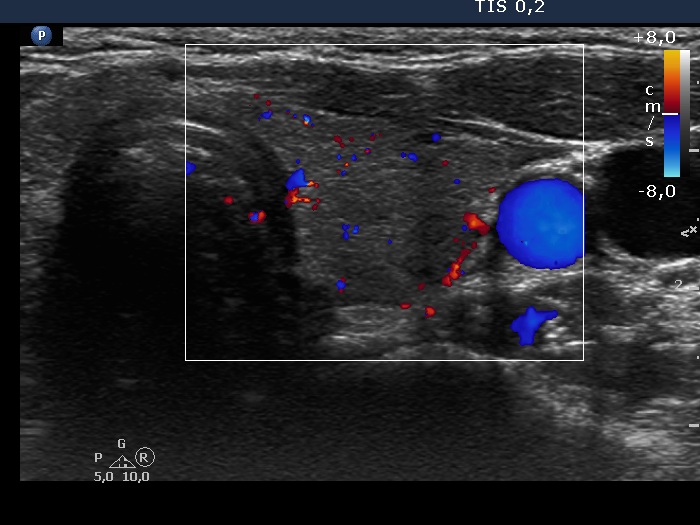

Left lobe, transverse scan, color Doppler mode. The vascularization is average.